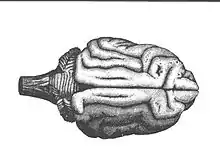

L'électrophysiologie reçut une nouvelle impulsion avec la description de l’excitabilité électrique du cerveau par Eduard Hitzig et Gustav Fritsch. On avait longtemps considéré le cerveau comme non-excitable : Humboldt avait constaté avec déception que l’excitation électrique du cerveau n'a aucune action mesurable. Mais en 1870 Hitzig et Fritsch décrivirent que « par injection de certains courants galvaniques dans la partie postérieure du cerveau, on obtient de légers mouvements oculaires qui, par leur nature, ne peuvent être déclenchés que par excitation directe de centres cérébraux[20]. » Grâce à la vivisection, Hitzig und Fritsch purent dresser ainsi une topique des centres moteurs chez le Chien (cf. ill.). Ils ouvraient le crâne de l'animal et excitaient une à une les différentes zones de la cervelle. Ils purent ainsi montrer que l'excitation de certaines régions entraînent une réaction d'extrémités ou membres spécifiques, et qu'une petite modification du point d'application du courant s'accompagnait d'une modification de la réaction.